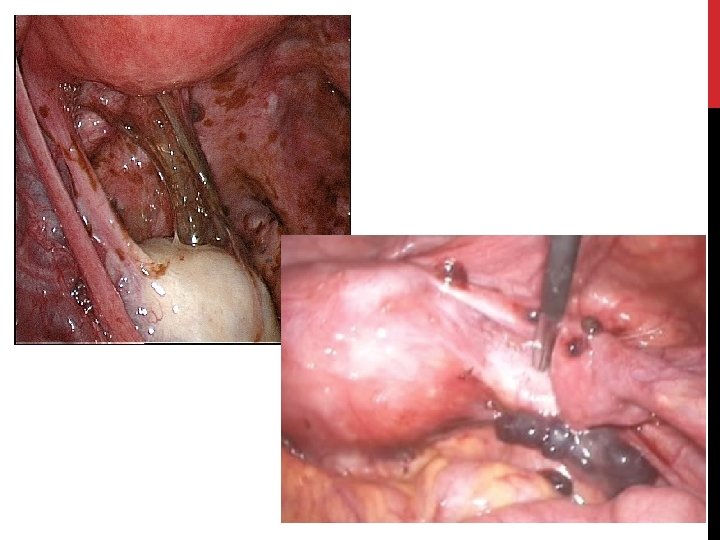

CŒLIOSCOPIE DIAGNOSTIQUE • • Examen diagnostique de référence. • • Peut méconnaitre des lésions surtout les lésions d’ESPP. Mais n’est pas requis avant la mise en œuvre du ttt chez toutes les patientes ! CRO: • Taille • Aspect macroscopique • Localisation • Infiltration • Adhérences • Un examen histologique est recommandé mais une histologie négative n’exclut pas la maladie. • En cas d’infertilité associée: • Si examens paracliniques normaux: probable endométriose minime ttt chirurgical améliore la fertilité. • Si découverte d’ESPP avec risques de complications chirurgicales: recours à la FIV sans chirurgie.

TRAITEMENT CHIRURGICAL • Peut être: • Radical (femmes ménopausées ou projet parental accompli) • Conservateur • Nécessité de prise en charge par des équipes expérimentées. • Indications: • Si douleurs pelviennes: • • • Échec ou CI au traitement médical. Incident annexiel aigu (torsion / rupture de kyste) Endométriose sous péritonéale profonde (atteinte digestive / urologique / nerveuse) • Endométriome: • • En cas de symptomatologie reliée au kyste. Associée à une infertilité (? )

TRAITEMENT CHIRURGICAL (2) • Évaluation pré opératoire minutieuse (cf bilan d’extension). • Privilégier la cœlioscopie. • Approche multidisciplinaire (gynécologue / urologue / chirurgien digestif). • Objectif: • • Exérèse de toutes lésions d’endométriose. • Améliorer la qualité de vie et les symptômes. • Limiter le risque de récidive. • Restaurer une anatomie « normale » . Traitement conservateur: • • Shaving rectal ou résection digestive. • Colpectomie. • Adhésiolyse. • Cystectomie partielle. • Réimplantation urétérale / Urétérolyse. • Interruption des LUS. • Neurolyse … Traitement radical: • • Exérèse de toutes lésions visibles + annexectomie bilatérale en vue d’instaurer une ménopause +- hystérectomie associée Hystérectomie seule non recommandée: risque élevé d’échec sur la douleur

TRAITEMENT CHIRURGICAL (3) • Résultats: • Amélioration de la qualité de vie. • Amélioration des symptômes douloureux. • Complications: • 0, 1 à 15% en fonction du stade de la maladie. • Dépendent de la chirurgie: • • • Risque de stomie provisoire. Fistule recto vaginale. Sténose colique / rectale. Fistules urétérale / dysurie / sténose urétérale. Abcès post opératoires….